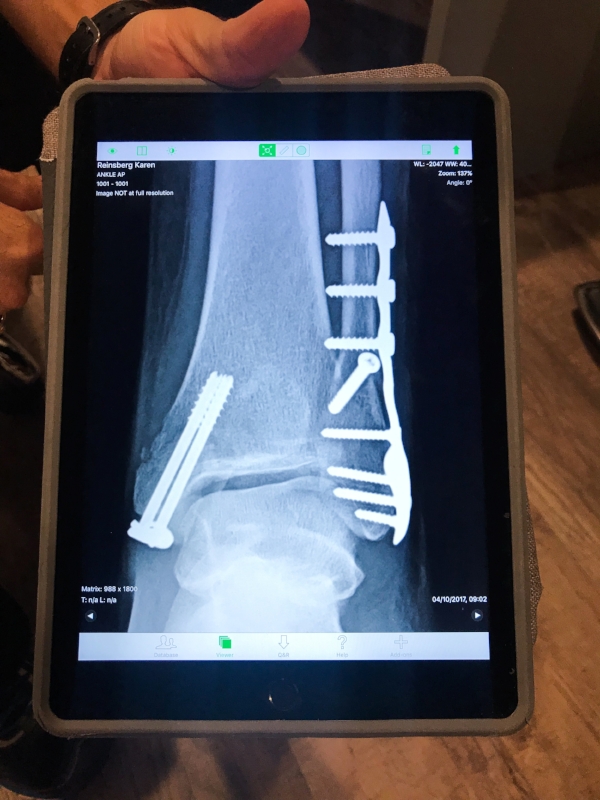

Six months later while traveling in Italy, she severely broke her ankle, resulting in extensive surgery, 10 screws being implanted in her foot and being wheelchair-bound for almost three months.

This has been a life saver for Karen’s ankle.

Even though her surgery was over 11 months ago, she still gets substantial swelling and pain.

Localized cryotherapy is a concentrated burst of cold air used to treat an area with pain and inflammation.

It makes an immediate impact to Karen’s foot and relieves Gavin’s back pain. It also helps provide her injured ankle with increased range of motion.